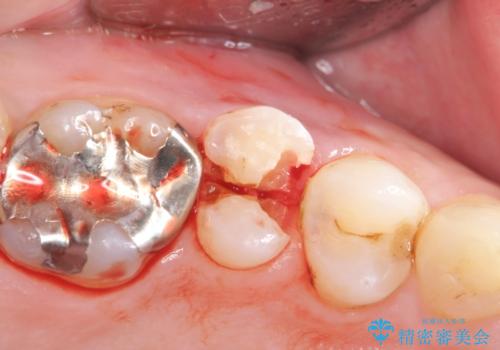

検査をしたところ、右上小臼歯に破折が見られ保存が難しい状況です。

抜歯を行い、咬合機能の回復を行いますが、咬合関係や非常に強い噛み合わせの問題をふまえ、咬合面をメタルにしたメタルボンドブリッジで治療を行うこととしました。

また噛み合わせが深くブリッジの強度が十分に確保できないことから、抜歯時に歯周外科を行うことで十分に安定したクラウン装着をできるような処置を行っています。

術前・術後でブリッジ治療をした部分の歯肉ラインを整えたことで安定したブリッジを製作することができました。